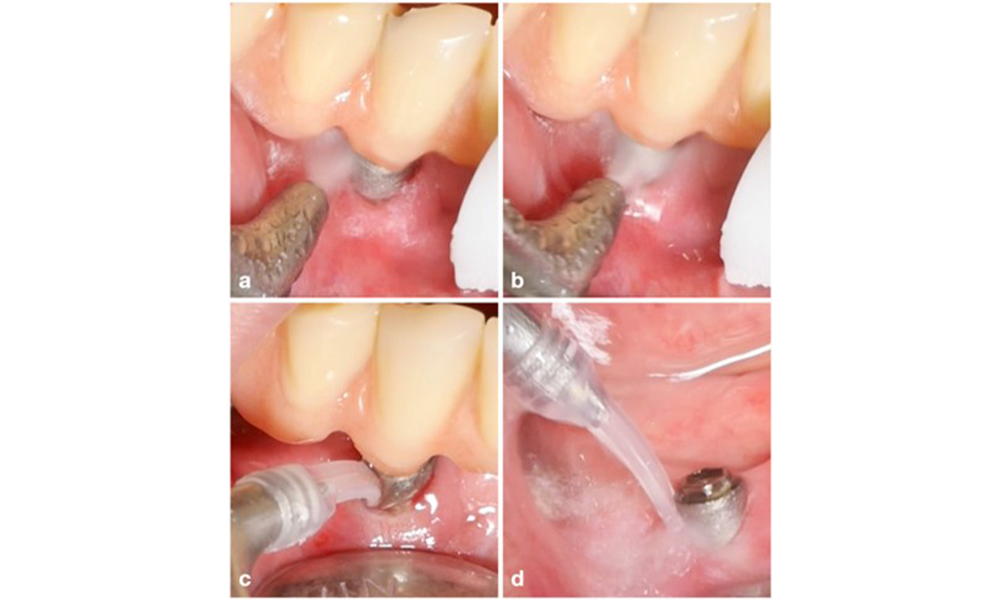

Das Behandlungskonzept der periimplantären Mukositis ist mit der Gingivitistherapie vergleichbar. Die wichtigste Maßnahme ist eine professionelle Plaquekontrolle mit dem Ziel einer mechanischen Entfernung des Biofilms ohne Veränderungen am Implantat oder an der Abutmentoberfläche. In der Literatur werden verschiedene Methoden unter Verwendung mechanischer Mittel beschrieben: Küretten, Schall- und Ultraschallscaler, Luftpoliergeräte, Laseranwendungen usw. mit oder ohne antimikrobielle Wirkstoffe. Derzeit liegen keine konsistenten Belege vor, dass eine Methode den anderen überlegen ist, und eine Behandlung der periimplantären Mukositis mit systemischen Antibiotika wird nicht empfohlen (Dommisch et al. 2022; Gennai et al. 2023; Hallström et al. 2012; Herrera et al. 2023; Verket et al. 2023).

Die Wahl der Mittel hängt von den klinischen Gegebenheiten wie zum Beispiel Zahnstein im Unterschied zu weichen Belägen ab. Bei Zahnstein sollten als Erstes Titan- bzw. Kunststoffküretten oder Ultraschallscaler mit speziell geformter Spitze zum Einsatz kommen, gefolgt von einem Luftpoliergerät (Abb. 7). Bei ausschließlich weichen Belägen ist ein Luftpoliergerät allein unter Umständen ausreichend. Luftpoliergeräte sind bediener- und patientenfreundlich und mindestens so wirksam wie Standardinstrumente (Schwarz et al. 2015a).